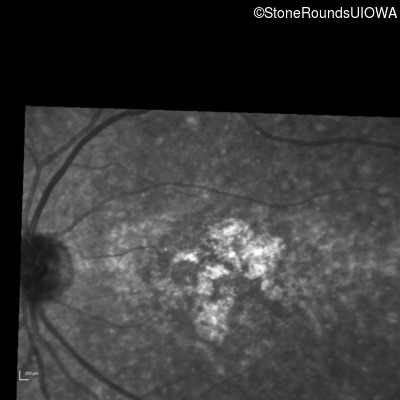

Infrared Fundus Photograph - Right - 10/160

Exemplar

Infrared Fundus Photograph - Left - 10/125